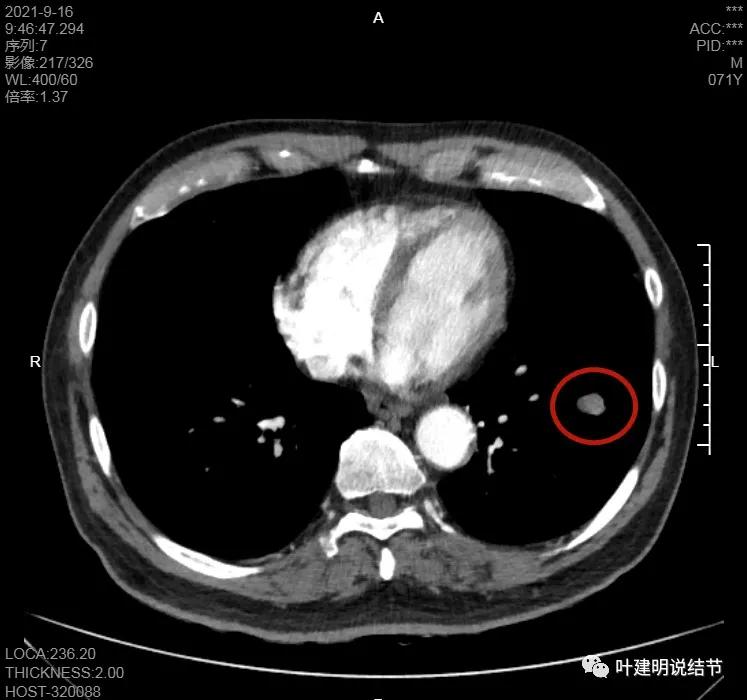

肺门区淋巴结挤压附近肺血管,但似乎示见肿瘤侵犯破坏血管壁

淋巴结巨大,部分包绕肺血管,但仍未见明显侵犯血管壁

肺血管受压明显,气管内壁感觉也是光滑的

以上诸图均示肿大淋巴结挤压肺血管,但未见确切侵犯破坏,支气管内壁也感觉是光滑的,没有肿瘤突向管腔

这样质地不硬,缺乏收缩力的原发灶,实性的,但却有明显的淋巴结转移,我首先想到的是小细胞肺癌,但小细胞肺癌容易广泛的纵隔淋巴结转移而且融合成团,这个病例只有肺门区的肿大淋巴结,不是特别符合。另外一个就是类癌,不典型类癌可以质软,缺乏破坏力,但却是恶性的,会转移。